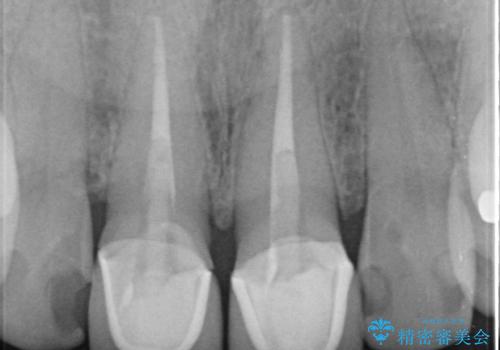

- 上顎の前から2番目の歯の古い樹脂をセラミックにしたいといらっしゃった方の症例です。

古い樹脂を除去後、オールセラミッククラウンによる補綴を行いました。

今回用いたオールセラミッククラウンはジルコニアフレームという白い素材の上にセラミックを盛っているため、審美性が非常に高いのが特徴です。